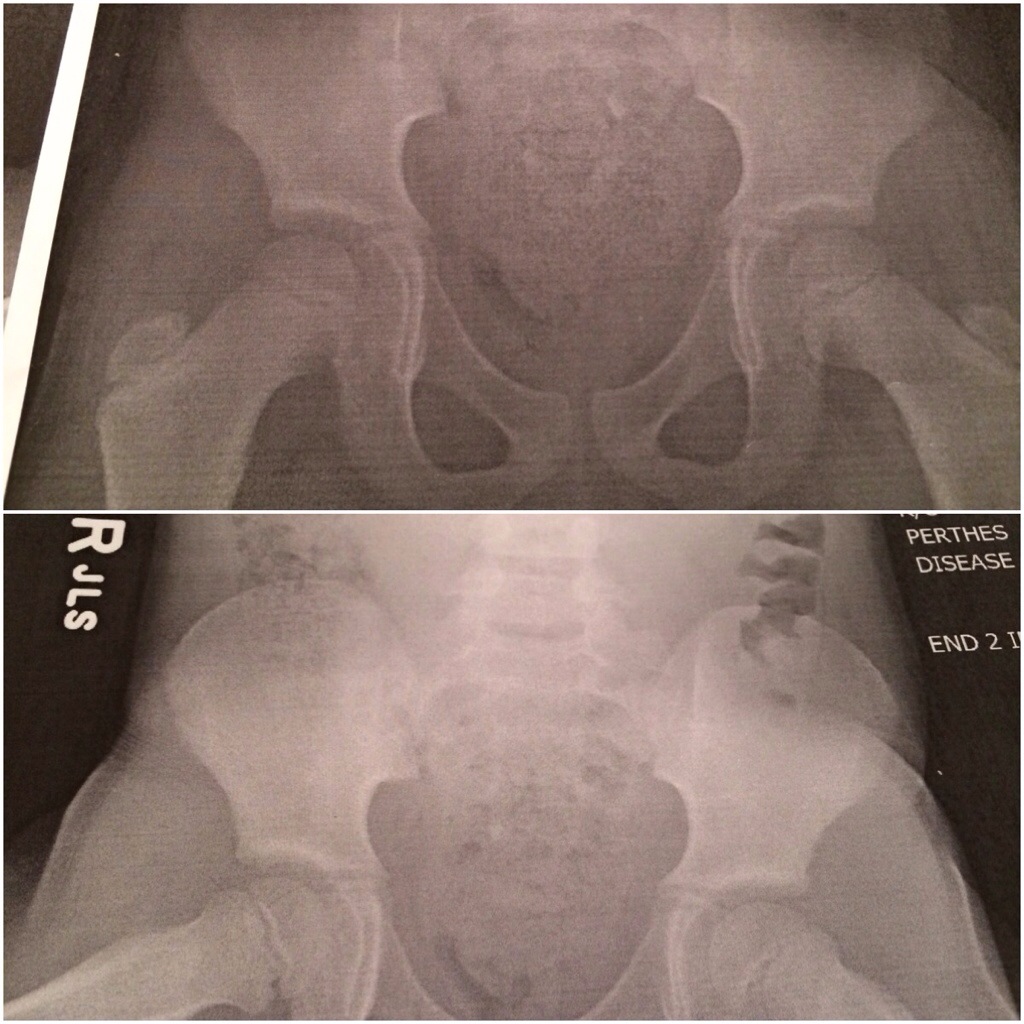

Soon after the neighborhood gathering (which was so much fun)… I was supposed to head up to the track meet but I took my 3rd daughter to the Insta-care for an X-ray appointment to check out her leg. She has the symptoms of Perthes Disease… The doctor took x-rays of her (the Doc was so amazing and so good with my daughter)!

They checked out her x-Ray and ruled out Perthes disease! π I was relieved! The lady printed off my daughter’s x-Ray and gave her a copy. She was so excited!